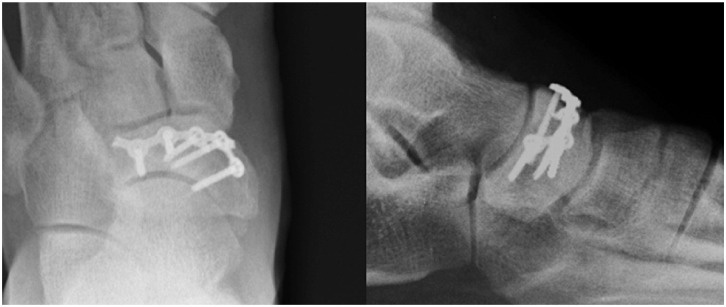

Surgical Treatment of Symptomatic Osteochondral Lesions of the Foot: A Contemporary Review.